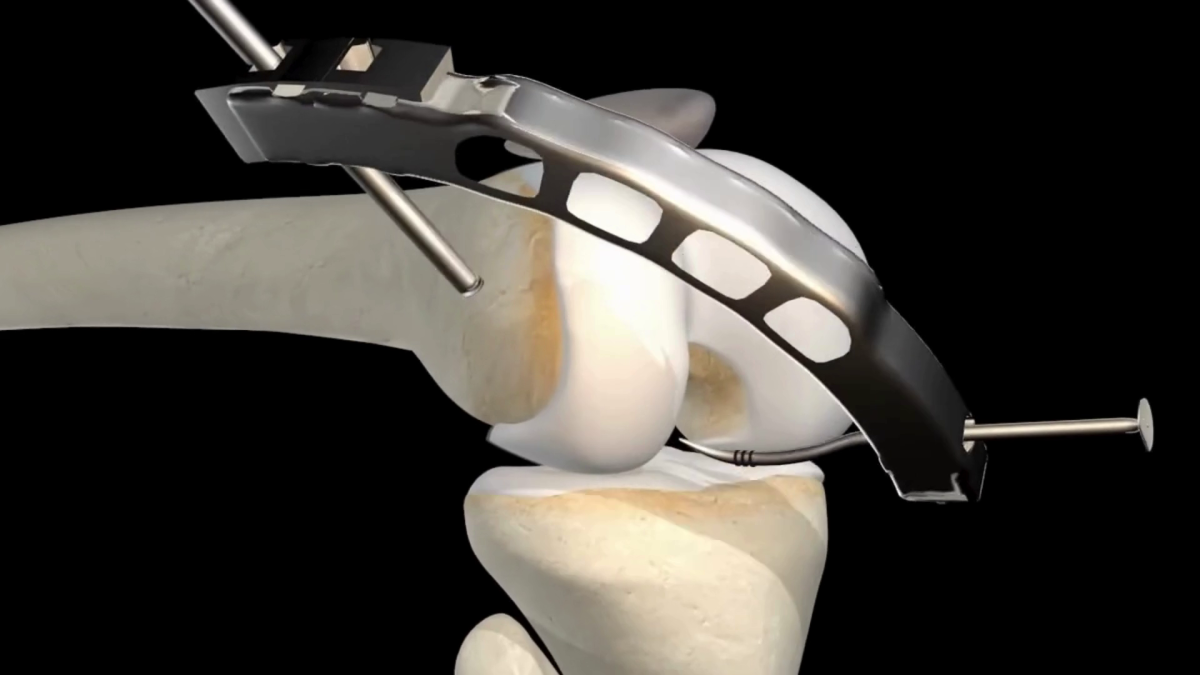

- 3D Dental Animation for procedures like cleaning, cavity filling, root canals, etc.

I have extensive experience in dental visualization and animation, ensuring that every project is accurate, professional, and visually appealing. I use advanced software to deliver high-quality videos tailored to your specific needs.

Tagged : 3d dental animation, 3d medical animation, dental models for oral health explainer, surgical animation, tray whitening